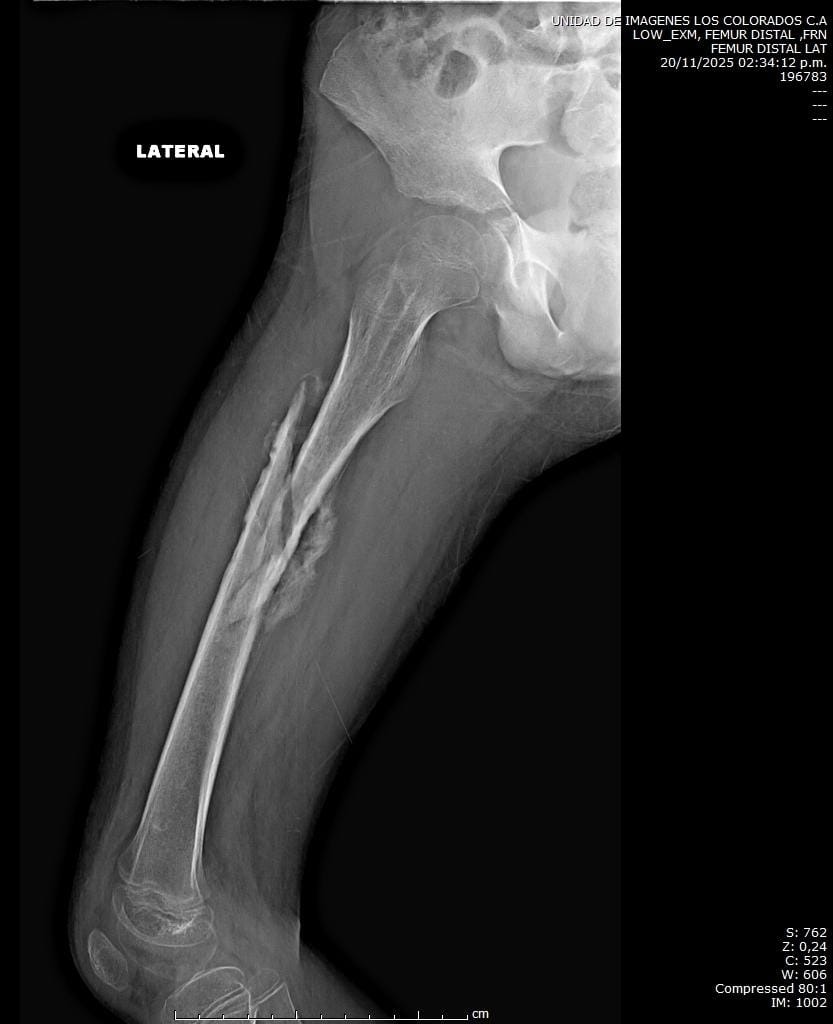

My name is Mariana Segovia, and I would like to share the difficult situation my son Martin, a nine-year-old boy full of energy and dreams, is currently facing. Recently, he suffered a severe femur fracture due to a twisting injury. Since then, we have been facing a challenging battle.

Martin has had to undergo three surgeries. The first two were unsuccessful and, unfortunately, led to a bone infection. In the third operation, the doctors had to remove 7 cm of bone and insert a spacer with surgical cement containing antibiotics to fight the infection, while also ensuring that the necessary space is preserved for future surgeries.